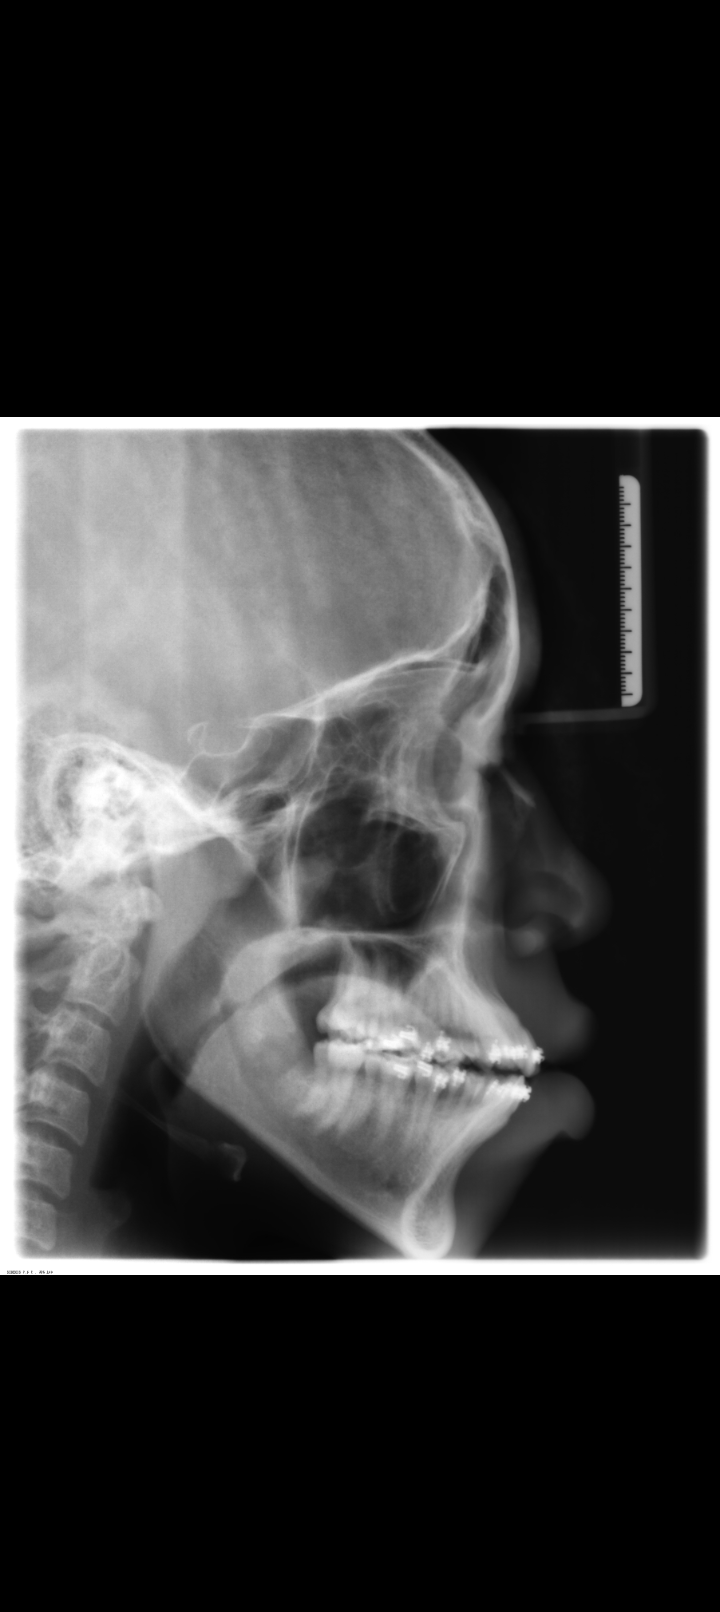

Lefort 2 to fix bimaxillary protrusion then braces to fix crooked teeth?

Lefort 2 to fix bimaxillary protrusion then braces to fix crooked teeth?